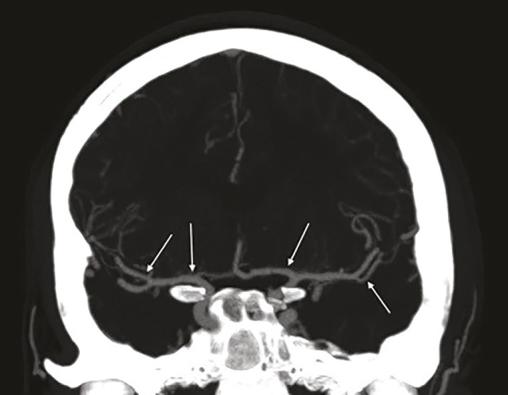

Le patient bénéficie d’un traitement oral par nimodipine pendant quatre semaines. L’évolution est favorable, avec disparition de la symptomatologie et des anomalies vasculaires sur l’imagerie réalisée à six semaines (fig. 2).